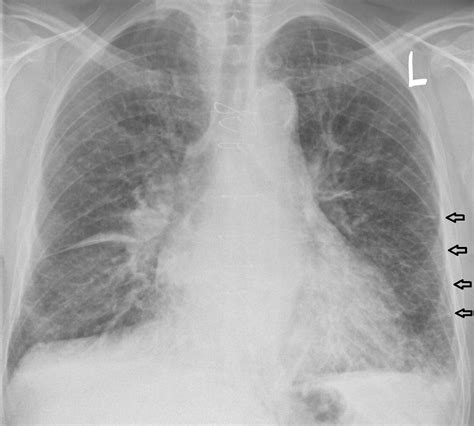

• Pleural Effusions: Fluid collecting in the pleural space, often bilateral but potentially unilateral, commonly seen in congestive heart failure.

While the Pulmonary Edema Cxr is excellent at confirming the presence of fluid, determining the etiology is equally important. Cardiogenic pulmonary edema is typically associated with a widened cardiothoracic ratio (cardiomegaly) and vascular redistribution. In contrast, non-cardiogenic pulmonary edema, often seen in Acute Respiratory Distress Syndrome (ARDS), usually presents with a normal heart size, patchy or peripheral infiltrates, and an absence of pleural effusions.

Clinicians utilize the X-ray in conjunction with lab tests like Brain Natriuretic Peptide (BNP) to make a definitive diagnosis. If the heart shadow is enlarged, it strongly suggests a cardiac origin, whereas a normal-sized heart with widespread bilateral infiltrates warrants an investigation into sepsis, transfusion-related lung injury, or other non-cardiac triggers.

To obtain an accurate Pulmonary Edema Cxr, technical factors must be optimized. Portable bedside chest X-rays, common in critical care settings, are often performed in an anteroposterior (AP) projection. This projection can artificially magnify the heart size, making it difficult to differentiate mild cardiomegaly from normal variants. Therefore, standardized positioning is vital for consistent interpretation.

High-quality images allow for the visualization of delicate structures such as the fissures. Increased fluid in the interlobar fissures, known as a "fissural thickening," is another reliable indicator of interstitial pulmonary edema. Furthermore, the quality of inspiration affects the appearance of the lung fields; poor inspiration can create an artificial appearance of crowding of the bronchovascular markings, potentially mimicking mild congestion.